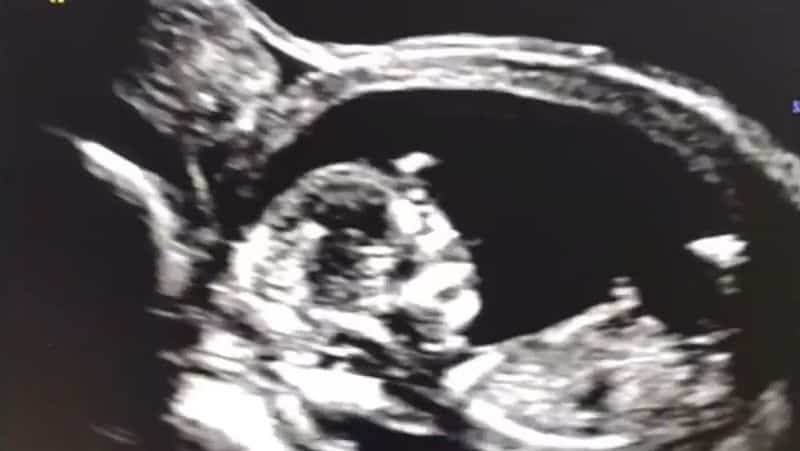

Die Frau in folgendem Video wurde während der Schwangerschaft mit dem Gen-Medikament «geimpft». Die zweite Dosis erhält sie am 8. Dezember 2021. Zu diesem Zeitpunkt ist sie in der 12. Schwangerschaftswoche. Am 4. Januar, als sie zum nächsten Ultraschall geht, ist ihr Sohn tot. Die Messungen ergeben, dass er unmittelbar nach der Gen-Behandlung der Mutter gestorben sein muss, weil er nach der 12. Woche nicht mehr gewachsen ist…